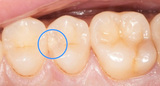

- 初期虫歯: 歯のエナメル質に小さな変色や斑点が現れます。この段階では痛みはほとんど感じませんが、歯の表面が酸によって溶け始めています。